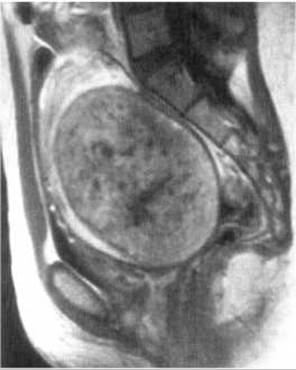

Пухлини матки можуть бути доброякісними і злоякісними. Із доброякісних пухлин частіше зустрічається фіброміома, яка утворюється внаслідок гіпертрофії і проліферації елементів сполучної та м’язової тканин. Під час УЗД Фіброміома матки проявляється її збільшенням, деформацією і додатковими утворами, частіше зниженої ехогенності. Метросальпінгографічно за наявності фіброміоми порожнина матки деформована, у ній визначається округлий дефект наповнення з чіткими рівними контурами, на відміну від раку тіла матки, який дає нерівні нечіткі контури (мал. 262). Магнітно-резонансна томографія дозволяє краще, ніж УЗД, КТ і метросальпінгографія визначити кількість, розміри та глибину залягання фіброміоми (мал. 263). Інтенсивність МР-сигналу залежить від переважання у будові пухлини фіброзної чи м’язової тканини, а також від наявності некрозів і порожнин розпаду.

Мал. 263. Фіброміома матки на МРТ (Т1-зважене зображення).